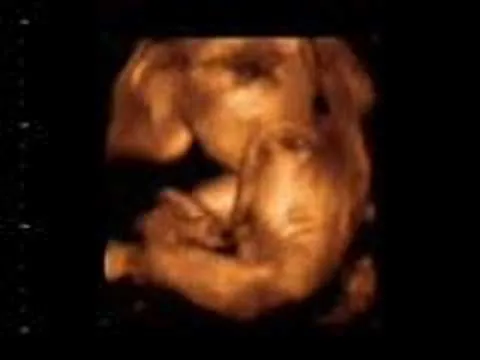

Imágenes de un bebé de 24 semanas

SEMANA 24: El bebé ya te oye y abre los ojos | Club Madres